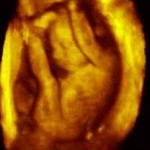

تثاؤب الجنين في بطن الأم عملية مرتبطة بنموه

قال باحثون قاموا بدراسة فحوصات بتقنية التصوير الرباعي الابعاد اجريت على 15 جنينا معافا في بطون امهاتهم إنهم يعتقدون ان التثاؤب عملية مرتبطة بنمو الجنين وهو ما قد يمنح الاطباء طريقة جديدة لتقييم صحة الاجنة.

واجرى الباحثون هذا باستخدام تقنية التصوير الرباعي الابعاد بالفيديو لفحص جميع المرات التي فتح فيها الاجنة افواههم.

واجريت الدراسة على ثمانية اجنة من الاناث وسبعة ذكور في الفترة من 24 إلي 36 اسبوعا من الحمل. ووجد الباحثون إن التثاؤب تراجع من الاسبوع الثامن والعشرين للحمل وانه لم يكن هناك اختلاف واضح في طريقة التثاؤب بين الذكور والاناث.